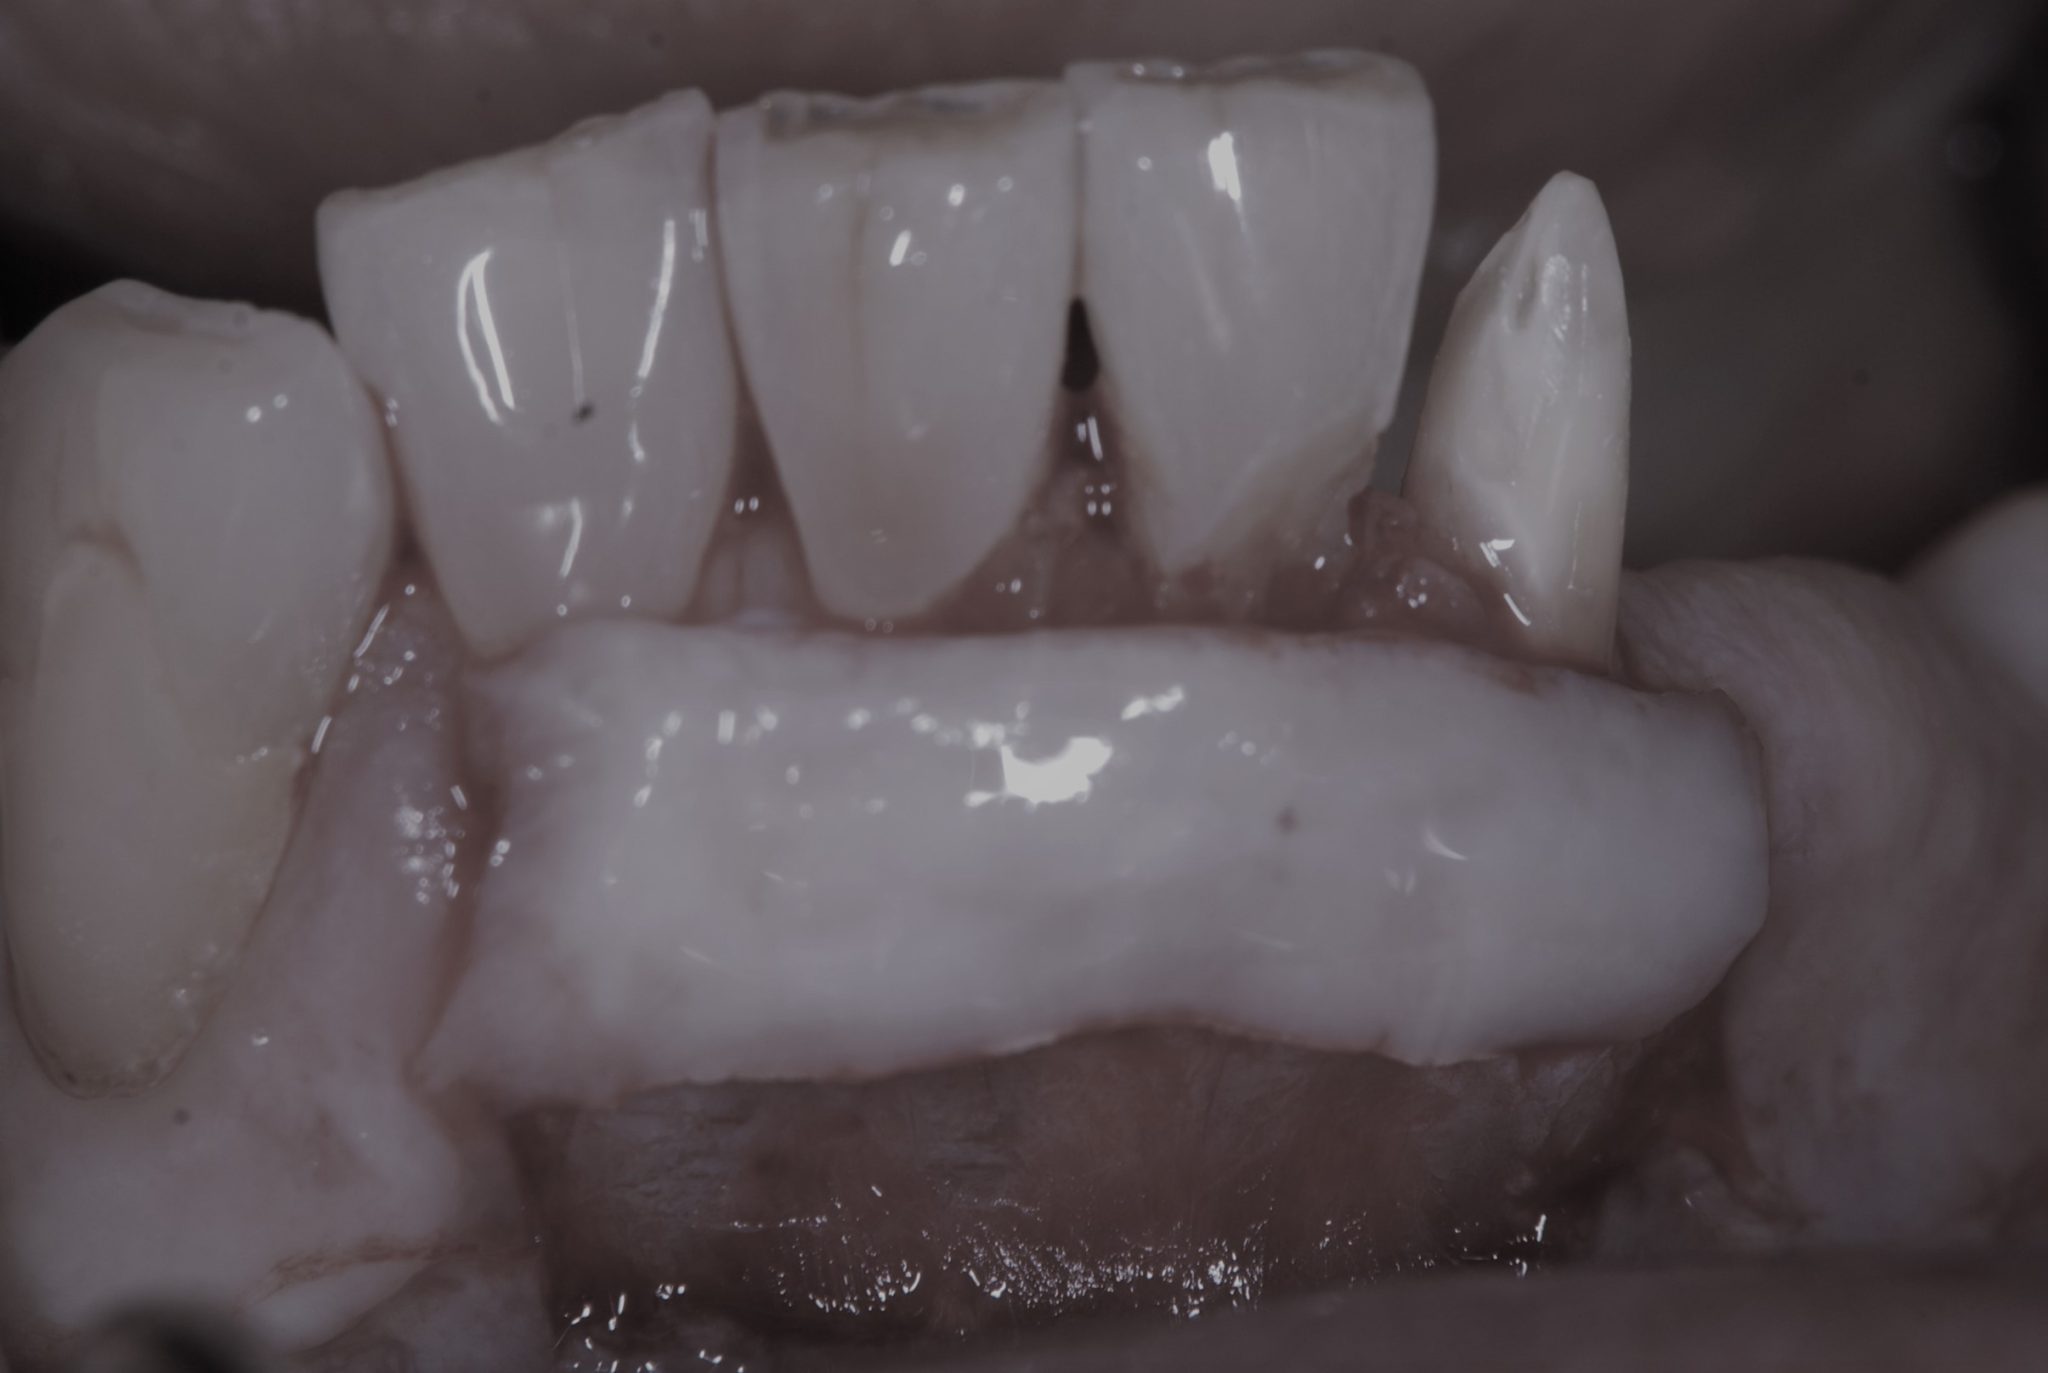

• 治療後

採取した上皮を薄い歯茎の部分に移植し、縫合する。

(遊離歯肉移植術)

治りを待って、歯の形を樹脂の詰め物で整えた。

見た目の回復はもちろん、歯茎が分厚くなったことで歯ブラシをしっかりと当てられるようになり、虫歯の予防も期待できる。